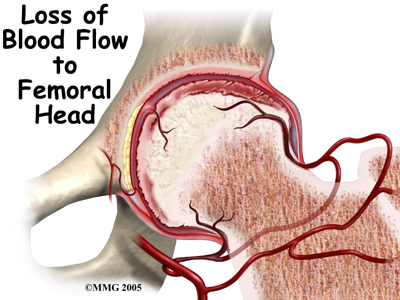

Legg-Calvé-Perthes disease typically affects boys between the ages of five and ten. It is also called osteonecrosis and avascular necrosis of the hip. It literally means death of bone. The ball of the hip dies because the blood supply has been cut off. When this happens, the femoral head and acetabulum will change their shapes over one to three years. The ball of the femur will flatten out. This problem with the hip is often missed at first. It is frequently misdiagnosed as synovitis of the hip.